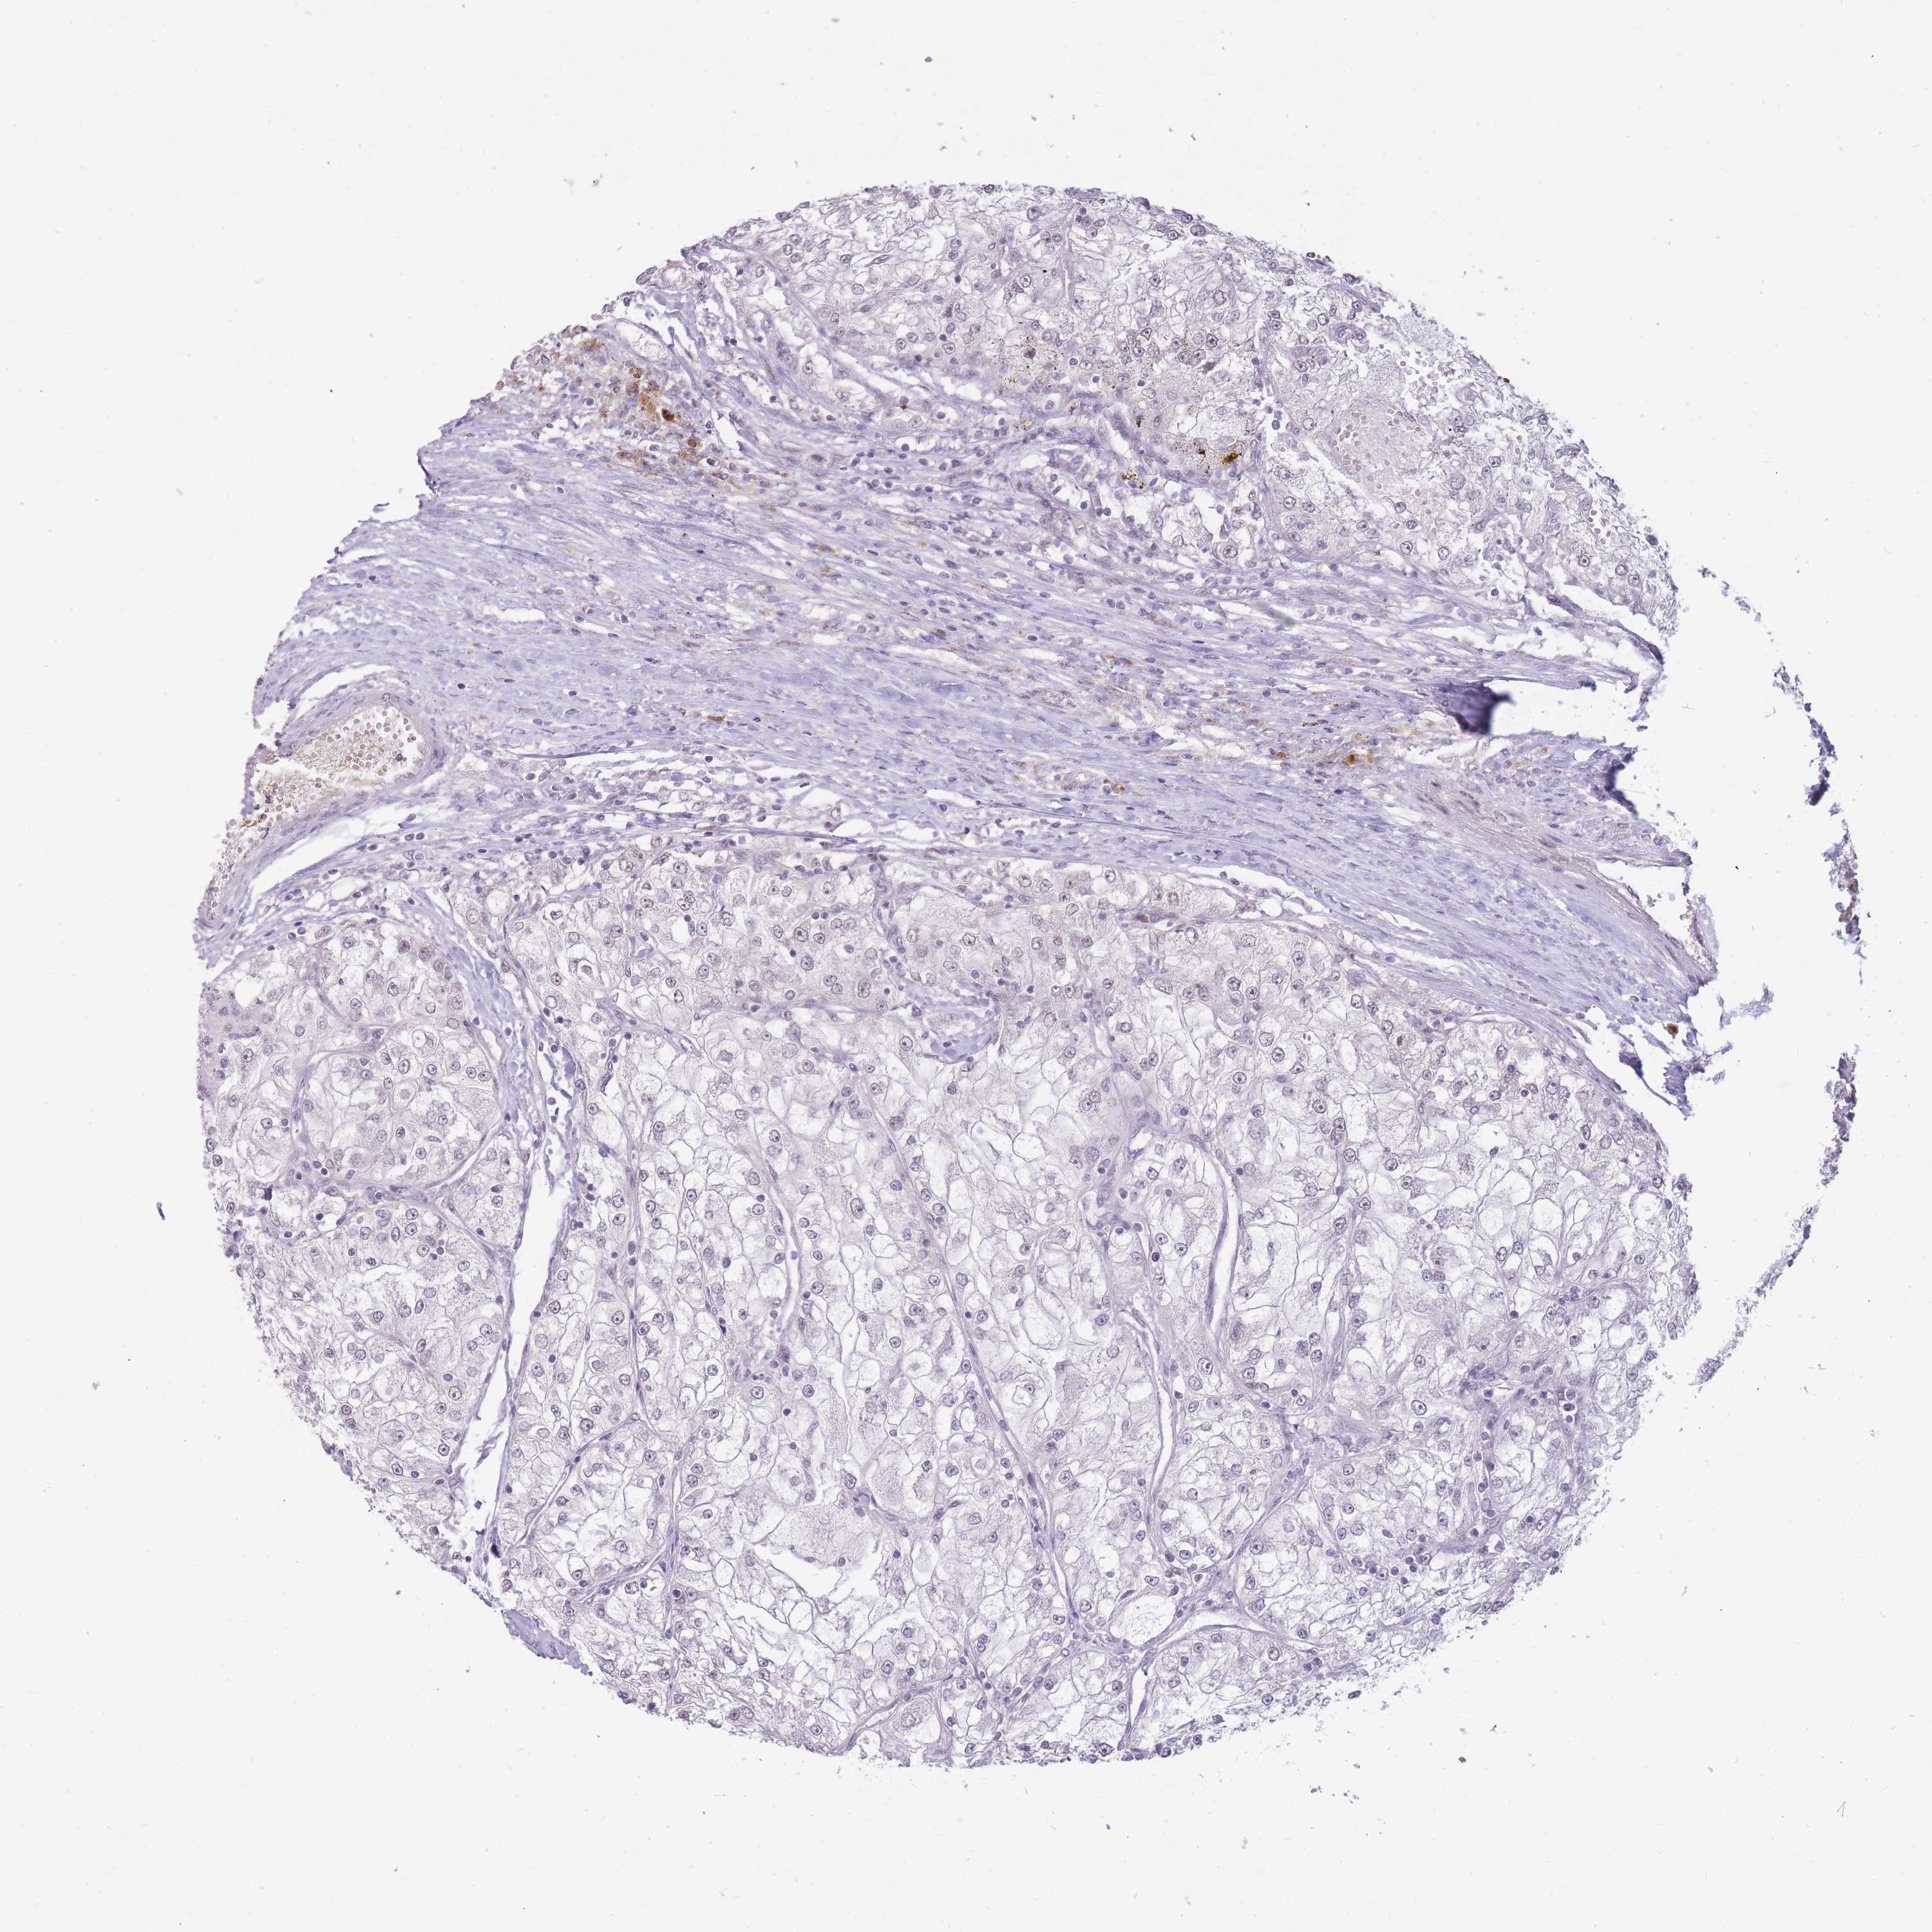

KIDNEY RENAL PAPILLARY CELL CARCINOMA (TCGA) - Interactive survival scatter ploti

The Survival Scatter plot shows the clinical status (i.e. dead or alive) for all individuals in the patient cohort, based on the same data that underlies the corresponding Kaplan-Meier plots. Patients that are alive at last time for follow-up are shown in blue and patients who have died during the study are shown in red.

The x-axis shows the expression levels (FPKM) of the investigated gene in the tumor tissue at the time of diagnosis. The y-axis shows the follow-up time after diagnosis (years). Both axes are complimented with kernel density curves demonstrating the data density over the axes. The top density plot shows the expression levels (FPKM) distribution among dead (red) and alive patients (blue). The right density plot shows the data density of the survived years of dead patients with high and low expression levels respectively, stratified using the cutoff indicated by the vertical dashed line through the Survival Scatter plot. This cutoff is automatically defined based on the FPKM cutoff that minimizes the p-score. The cutoff can be changed by dragging the vertical line or by entering a cutoff value in the square labeled "Current cut-off".

Under the Survival Scatter plot the p-score landscape (black curve; left axis) is shown together with dead median separation (red curve; right axis). Dead median separation is the difference in median mRNA expression between patients who have died with high and low expression, respectively. It is calculated as follows: median FPKM expression of dead patients with high expression - median FPKM expression of dead patients with low expression. This is intended to aid the user in visually exploring custom cutoffs and the associated p-scores and dead median separation.

Individual patient data is displayed and can be filtered by clicking on one or more of the category buttons on the top of the page. Categories describing expression level and patient information include: high, low, alive, dead, female, male and tumor stages. The scale of the x-axis can be toggled between linear and log-scale by clicking on the "x log" button. Mouse-over function shows TCGA ID, patient information and mRNA expression (FPKM) for each patient.

& Survival analysisi

Kaplan-Meier plots summarize results from analysis of correlation between mRNA expression level and patient survival. Patients were divided based on level of expression into one of the two groups "low" (under cut off) or "high" (over cut off). X-axis shows time for survival (years) and y-axis shows the probability of survival, where 1.0 corresponds to 100 percent.

HNRNPUL1 is not prognostic in Kidney Renal Papillary Cell Carcinoma (TCGA)